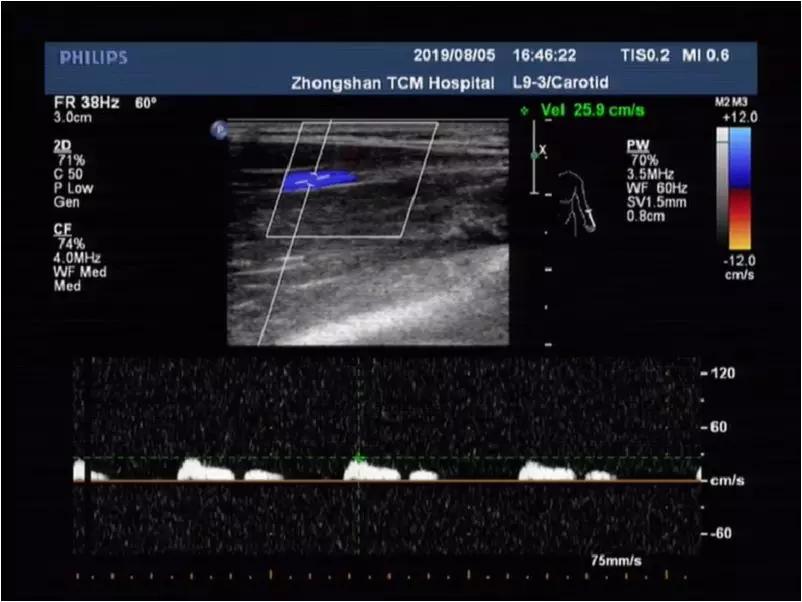

上举体位:桡动脉频谱血流低速低阻,收缩期时相延长